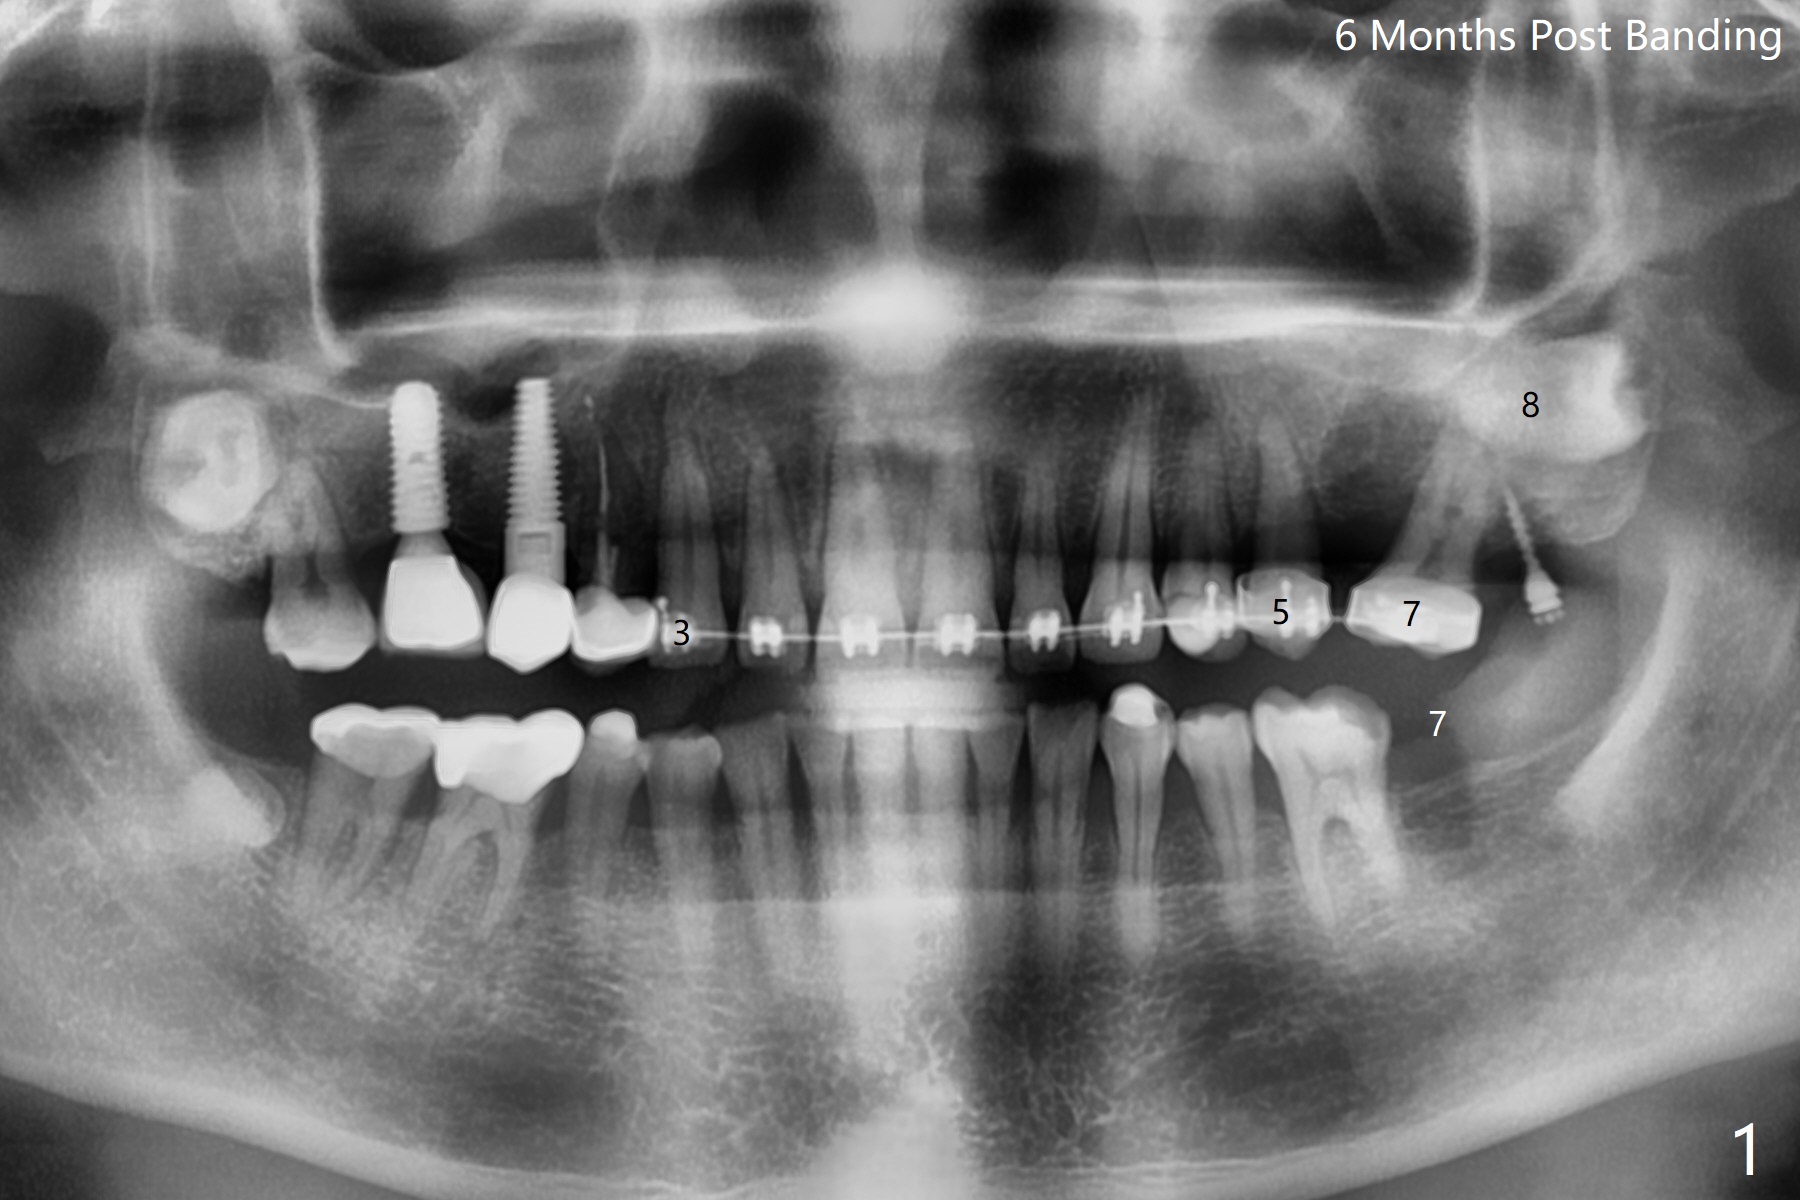

为了在左上6,左下7种植,使用右上3至左上5作为支抗推左上7远中,但是六个月效果不显著(图一),CT显示阻生牙(图一,二:8)没有阻挡。7远中植入1.6x8毫米微型植体,不过接近7根尖(图三),微型植体应该改变角度,而且往远中颊侧移位。最后效果不错(图四),植体马上启用(图五),而且同时取模做左下7导板。在微型植体牵引下,左上7的确往远中移位(图六,与图四对比),但是植体松动,马上植入3x10(2)毫米一段式植体,由于8阻挡,后者没有完全就位,稳定性差,没有启动。几天后也脱落。病人急着完成治疗,因为咀嚼困难。补救方法便是拔除阻生牙9(图七:x),让植体完全就位。切开后发现牙槽嵴处严重骨质吸收缺损(图八:D),离7很近,不适合种植。拔除8后(图九:S(socket)),两处植骨(粘性,图十),覆盖PRF膜,缝合。矫正九个月6空间相当双尖牙(图十二),还想增加2毫米才种植,病人急于完成治疗,所以再次植入微型植体,不同之处是切开,发现7远中颊侧骨质密度低(用探针),因此微型植体在腭侧植入(图十一:P),扭力似乎高,1.6x8毫米植体仿佛植入8牙槽窝(图十二:红虚线)。微型植体牵引一个月,磨牙缺牙间隙大约前磨牙大小,准备在远中(图十三)植入直径小植体(图十四),当后者整合时,用它继续推7。